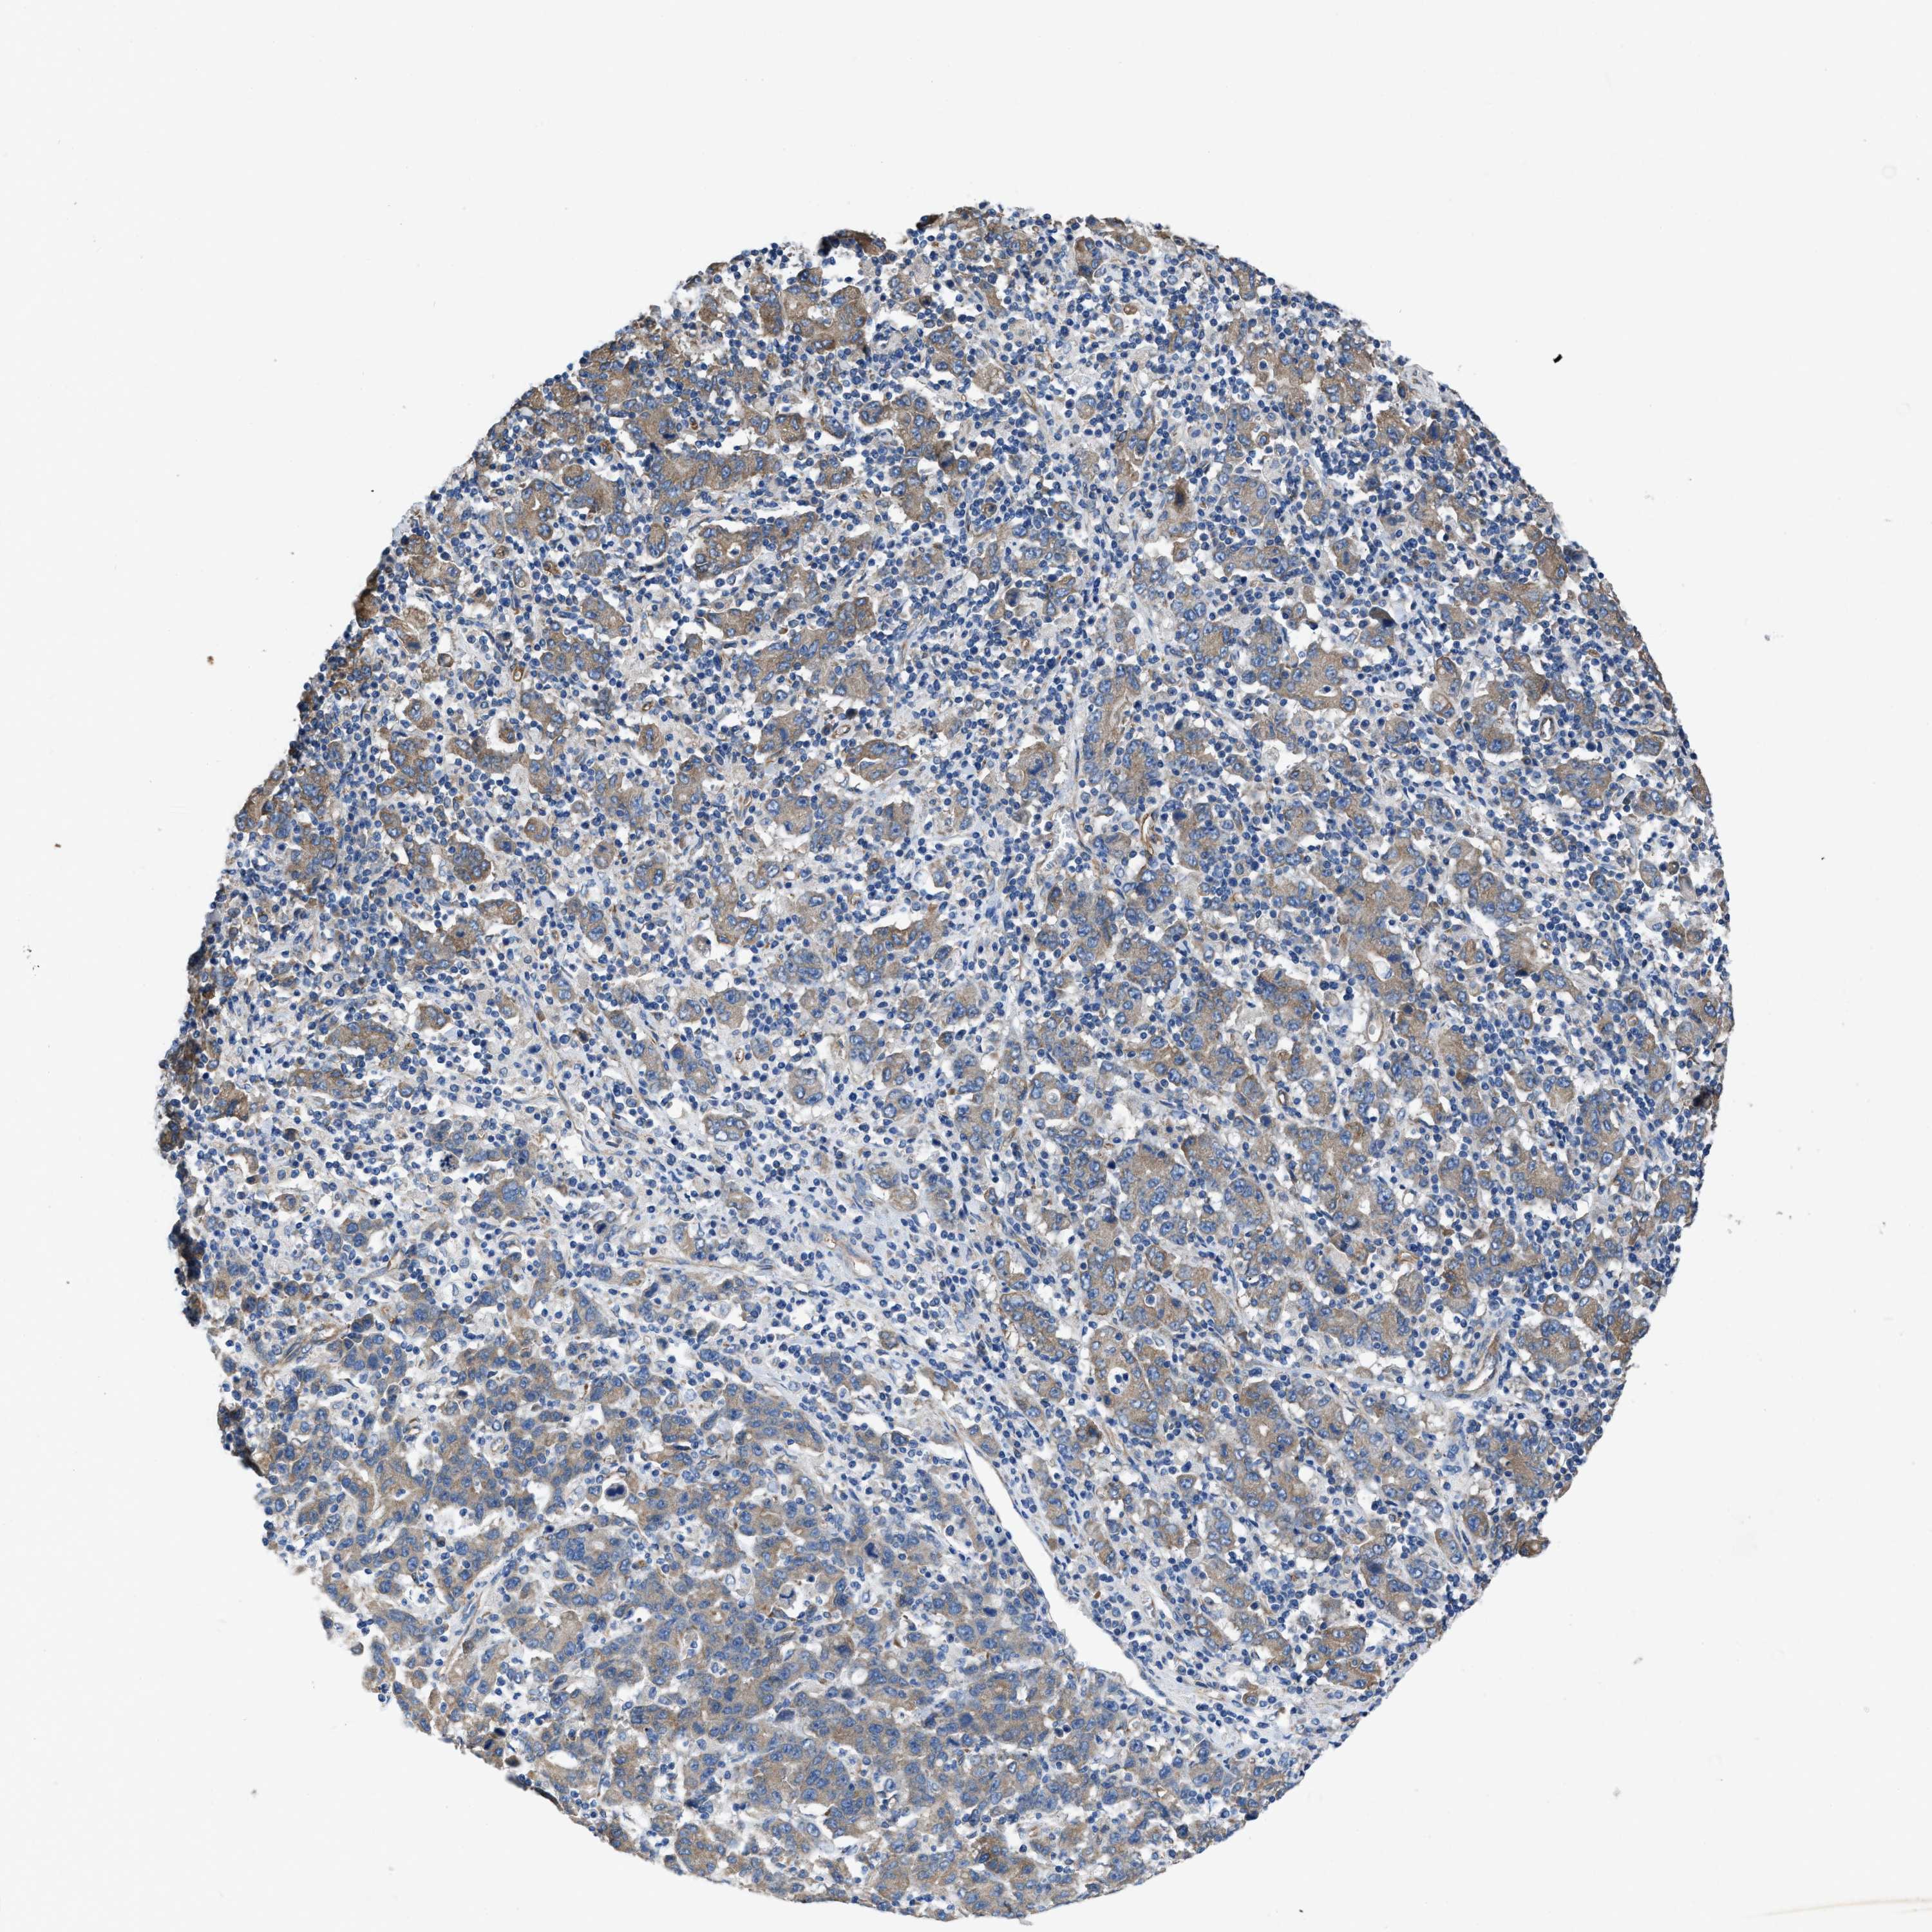

STOMACH CANCER - Protein expressioni

A mouse-over function shows sample information and annotation data. Click on an image to view it in a full screen mode. Samples can be filtered based on level of antibody staining by selecting one or several of the following categories: high, medium, low and not detected. The assay and annotation is described here.

Antibody stainingi

Antibody staining in the annotated cell types in the current human tissue is reported as not detected, low, medium, or high, based on conventional immunohistochemistry profiling in selected tissues. This score is based on the combination of the staining intensity and fraction of stained cells.

Each image is clickable and will lead to virtual microscopy that enables deeper exploration of all samples and also displays staining intensity scores, fraction scores and subcellular localization as well as patient and tissue information for each sample.

Antibody HPA019179

Staining

High

Medium

Low

Not detected

Intensity

Strong

Moderate

Weak

Negative

Quantity

>75%

75%-25%

<25%

None

Location

Nuclear

Cytoplasmic/membranous

Cytoplasmic/membranous,nuclear

Adenocarcinoma, NOS